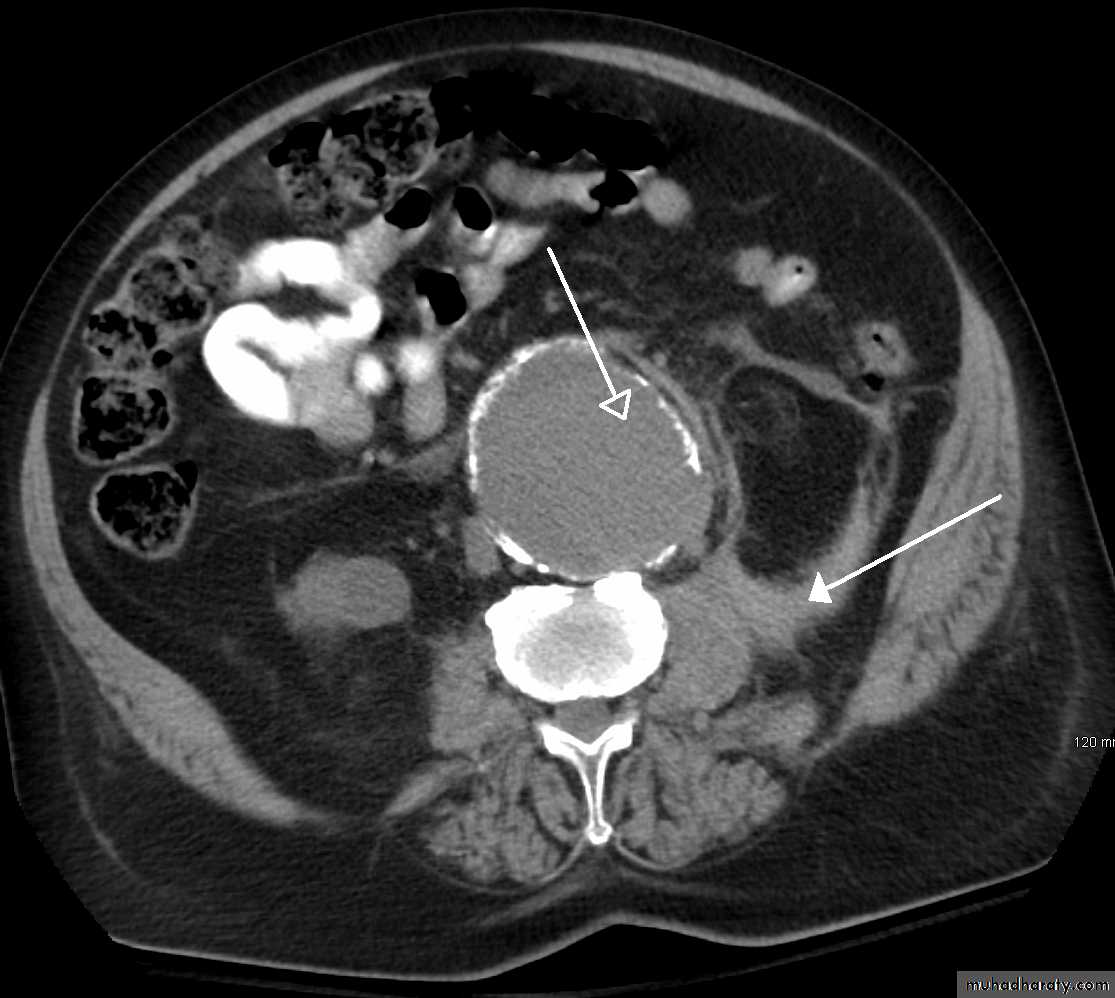

What is an aneurysm??An aneurysm is a localized, permanent dilatation of an artery greater than 1.5 times its normal diameter.

• CT and CT angiography

CT angiography: